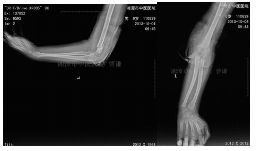

外院片如下:

杨氏四步复位法整复后拍片复查

治疗两月余拍片复查